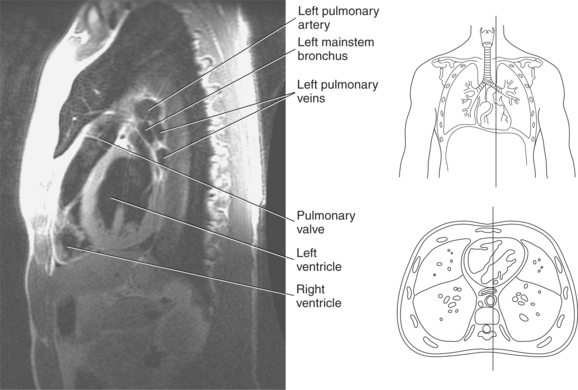

Blood travels to and from the heart through the great vessels, which include the aorta, pulmonary arteries and veins, and superior and inferior venae cavae (Figures 6.54 and 6.55). The aorta is the largest artery of the body and can be divided into the ascending aorta, aortic arch, and descending aorta. The ascending aorta begins at the base of the left ventricle at the level of the sternal angle, then curves superiorly and posteriorly as the aortic arch over the root of the left lung. The top of the aortic arch is approximately at T3 (Figures 6.56 and 6.57). The arch continues as the descending aorta posterior to the left bronchus and pulmonary trunk, on the left side of the vertebral body of T4 (Figures 6.58 and 6.59). The descending aorta passes slightly anterior and to the left of the vertebral column as it descends through the thoracic and abdominal cavities (Figure 6.60). While in the thoracic cavity, the descending aorta is commonly called the thoracic aorta, and while in the abdominal cavity, it is called the abdominal aorta. The pulmonary trunk is the origin of the right and left pulmonary arteries and lies entirely within the pericardial sac. It arises from the right ventricle and ascends in front of the ascending aorta, courses posteriorly and to the left, where it bifurcates at the level of the sternal angle (T4) into the right and left pulmonary arteries (Figures 6.61 through 6.63). The pulmonary trunk is attached to the aortic arch by a fibrous cord called the ligamentum arteriosum, the remnant of an important fetal blood vessel (ductus arteriosus) that links the pulmonary and systemic circuits during fetal development (Figures 6.54 and 6.61). The right pulmonary artery courses laterally, posterior to the ascending aorta and superior vena cava, and anterior to the esophagus and right mainstem bronchus, to the hilum of the right lung. At the root of the right lung, the right pulmonary artery divides into two branches, with the lower branch supplying the middle and inferior lobes and the upper branch supplying the superior lobe (Figures 6.61 through 6.64). The left pulmonary artery, shorter and smaller than the right, is also the most superior of the pulmonary vessels. It travels horizontally, arching over the left mainstem bronchus, and enters the hilum of the left lung just superior to the left mainstem bronchus (Figures 6.61 through 6.64). Within the lungs, each pulmonary artery descends posterolateral to the main bronchus and divides into lobar and segmental arteries, continuing to branch out and to follow along with the smallest divisions of the bronchial tree (Figures 6.61 and 6.64). Located inferior to the pulmonary arteries are the four pulmonary veins, two each (superior and inferior) extending from each lung to enter the left atrium (Figures 6.54, 6.55, 6.61, and 6.64 through 6.68). They commence in a capillary network along the walls of the alveoli, where they are continuous with the capillaries of the pulmonary arteries. The venous capillaries merge to form small vessels that unite successively to eventually form a single trunk for each lobe: three for the right and two for the left lung. Frequently the trunk from the middle lobe of the right lung unites with the trunk from the upper lobe, forming just two trunks on the right side prior to entering the left atrium. The right superior pulmonary vein collects blood from the upper lobe segments of the right lung and passes anterior and inferior to the right pulmonary artery, behind the superior vena cava. The right inferior pulmonary vein receives blood from the right lower lobes of the lung and crosses behind the right atrium to the left atrium (Figures 6.61 and 6.69 through 6.71). The left superior pulmonary vein receives blood from the left upper lobe of the left lung and courses anterior and inferior to the left main bronchus as it enters the left atrium. The left inferior pulmonary vein drains the inferior lobe of the left lung and passes toward the left atrium anterior to the bronchi (Figures 6.61 and 6.72 through 6.74). The pulmonary veins course more horizontally than the pulmonary arteries and are ultimately oriented toward the left atrium. At the root of the lungs, the pulmonary veins are anterior to the pulmonary arteries, which are anterior to the bronchus. While within the lungs, the branches of the pulmonary arteries are anterior to the bronchi, which are anterior to the pulmonary veins. The superior and inferior venae cavae are the largest veins of the body. The superior vena cava is formed by the junction of the brachiocephalic veins, posterior to the right first costal cartilage, and carries blood from the thorax, upper limbs, head, and neck (Figure 6.24). As it travels inferiorly, it is located posterior and lateral to the ascending aorta before entering the upper portion of the right atrium (Figures 6.54 through 6.59). The inferior vena cava is formed by the junction of the common iliac veins in the pelvis and ascends the abdomen to the right of the abdominal aorta and anterior to the vertebral column. It passes through the caval hiatus of the diaphragm and almost immediately enters the inferior portion of the right atrium (Figures 6.75 and 6.76).

The right atrium forms the right border of the heart and receives deoxygenated blood from the body via the superior and inferior venae cavae and from the coronary sinus and cardiac veins that drain the myocardium. A small muscular embryonic appendage, the right auricle, projects upward and toward the left from the right atrium, covering the root of the aorta (Figure 6.40). The right ventricle lies on the diaphragm and comprises the largest portion of the anterior surface of the heart. It receives deoxygenated blood from the right atrium and forces it into the pulmonary trunk for conveyance to the lungs. Projecting off the inferior surface of the ventricular walls are conical-shaped projections of cardiac muscle called papillary muscles that anchor the cusps of the tricuspid valve to the right ventricle (Figure 6.39). The left atrium lies posterior to the right atrium and is the most posterior surface of the heart. It also has an embryonic appendage, the left auricle, that projects to the left of the pulmonary trunk over the superior surface of the heart. The left atrium receives oxygenated blood directly from the lungs via the four pulmonary veins (two on each side). The left ventricle forms the apex, left border, and most of the inferior surface of the heart. It receives oxygenated blood from the left atrium and pumps it into the aorta for distribution throughout the systemic circuit. The myocardium of the left ventricle is normally three times thicker than that of the right ventricle, reflecting the force necessary to pump blood to the distant sites of the systemic circulation (Figures 6.41 through 6.52). Two papillary muscles project from the ventricular walls to anchor the bicuspid valve to the ventricle (Figures 6.39 and 6.47).

The semilunar valves are located at the junction where the ventricles meet the great vessels, separating the ventricles from the circulatory system. These valves are called semilunar because of their three crescent-shaped cusps and function to prevent the flow of blood back into the ventricles during ventricular relaxation. The pulmonary semilunar valve is located at the juncture of the right ventricle and pulmonary artery, and the aortic semilunar valve lies between the left ventricle and ascending aorta (Figure 6.51 through 6.53).